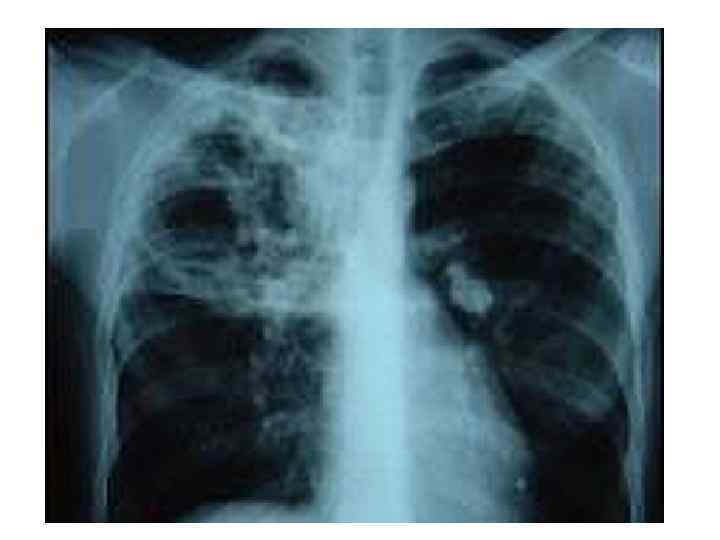

Варианты течения ТВГЛУ 1) с неосложнённым течением, 2) с осложнённым течением. • Клиническая картина неосложнённого ТВЛУ характеризуется симптомами интоксикации и наблюдается в современных условиях у 85% больных (В. А. Соколов). Рентгенологическая картина обусловлена изменениями корней лёгких, реже – средостения, при вовлечении в процесс нескольких групп ВЛУ. • Клиническая и рентгенологическая картина осложнённого ТВЛУ, характеризуется вовлечением в процесс бронхов, плевры, лёгких.